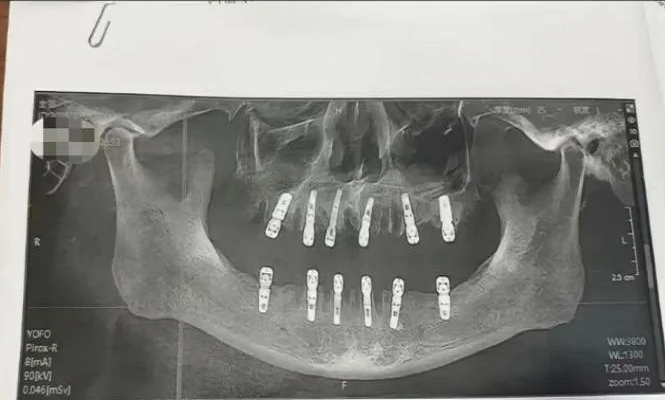

Trang Oddity Central đưa tin, cô Shu, cư dân của thành phố Vĩnh Khang, tỉnh Chiết Giang, Trung Quốc, gần đây đã nộp đơn khiếu nại một phòng khám nha khoa lên cơ quan y tế thành phố sau khi cha cô qua đời. Người phụ nữ này đưa ra bằng chứng cho thấy cha cô đã nhổ 23 chiếc răng và trồng 12 chiếc răng mới trong một lần, khiến ông tử vong chỉ 13 ngày sau đó.

Theo mẫu đơn đồng ý của bệnh nhân, cha của cô Shu thực tế đã nhổ 23 chiếc răng tự nhiên của mình trước khi khoan 12 lỗ vào xương hàm để trồng răng mới. Tất cả những điều này được thực hiện trong một ngày, điều đó có nghĩa là ông phải chịu đựng nỗi đau không thể tưởng tượng được sau khi thuốc tê hết tác dụng.

Theo hồ sơ của Phòng khám Nha khoa Dewei, việc nhổ 23 chiếc răng được thực hiện bởi một bác sĩ tên là Yuan, người có chuyên môn bao gồm điều trị tủy, nhổ răng khôn mọc ngầm và làm răng giả toàn hàm.